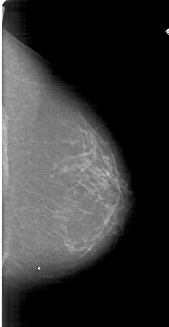

A_1800_1.LEFT_CC

LEFT_CC LINES 6841 PIXELS_PER_LINE 3466 BITS_PER_PIXEL 12 RESOLUTION 43.5 OVERLAY